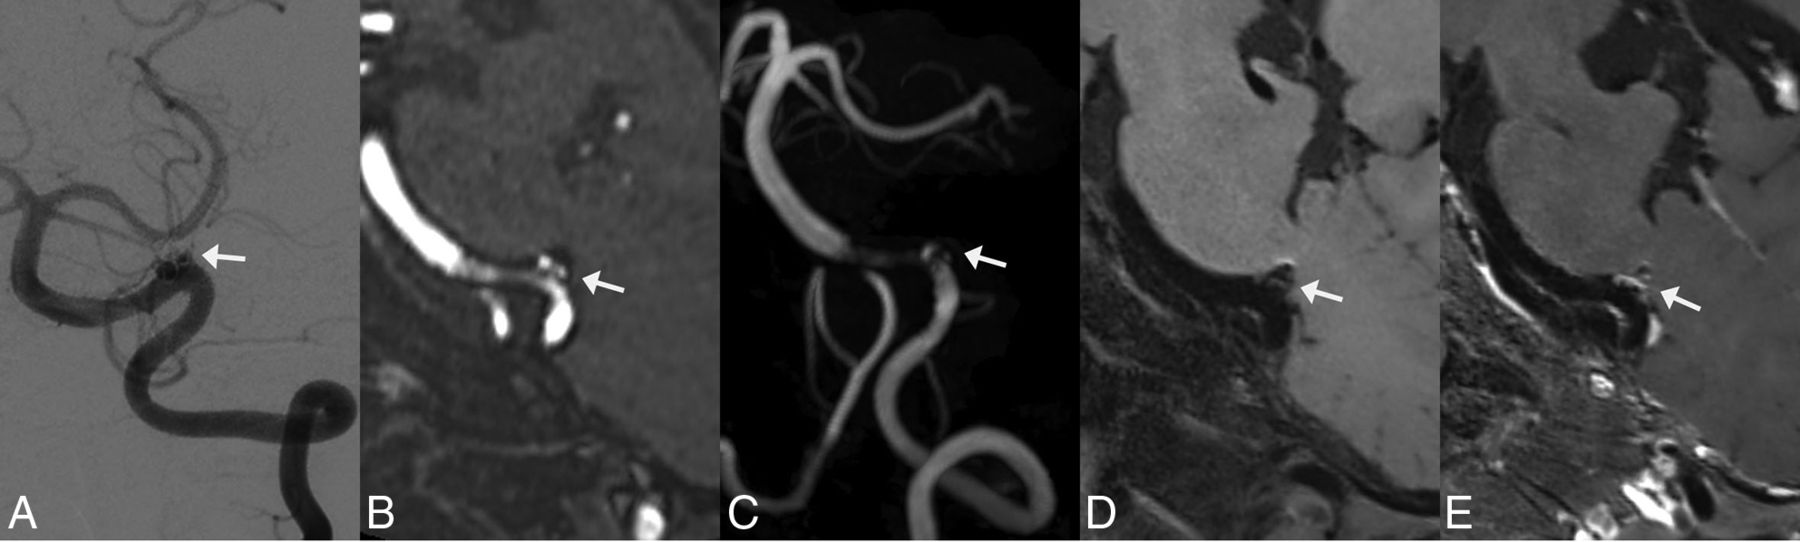

Follow-up images of a left vertebral artery dissecting aneurysm treated by LVIS stent-assisted coiling 6 months after the procedure. White arrows indicate the location of the aneurysm. A, DSA shows that the aneurysm involves incomplete occlusion and the stented artery is normal. B and C, MPR and MIP images of TOF-MRA show an aneurysm remnant. Moderate artifacts and a stenosis are observed at the stented artery on TOF-MRA. D and E, On pre- and postcontrast 3D T1-weighted SPACE, though no aneurysm remnant is observed, the stented artery is depicted well and indicates an absence of stenosis. The postcontrast image shows enhancement of the aneurysm wall, aneurysm lumen, and stented artery. The image quality score assigned by the 2 reviewers for TOF-MRA and 3D T1WI SPACE is 3/3 and 5/5, respectively.